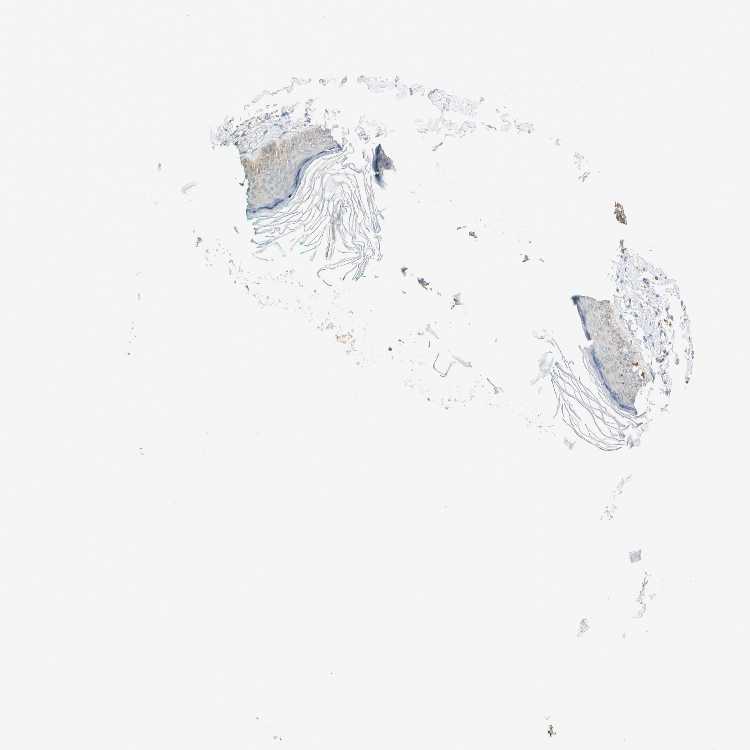

SKIN 1 - Antibody stainingi

Antibody staining in the annotated cell types in the current human tissue is reported as not detected, low, medium, or high, based on conventional immunohistochemistry profiling in selected tissues. This score is based on the combination of the staining intensity and fraction of stained cells.

Each image is clickable and will lead to virtual microscopy that enables deeper exploration of all samples and also displays staining intensity scores, fraction scores and subcellular localization as well as patient and tissue information for each sample.

Antibody HPA006139Antibody HPA006140

Langerhans LowMedium

Fibroblasts Not detectedNot detected

Keratinocytes LowLow